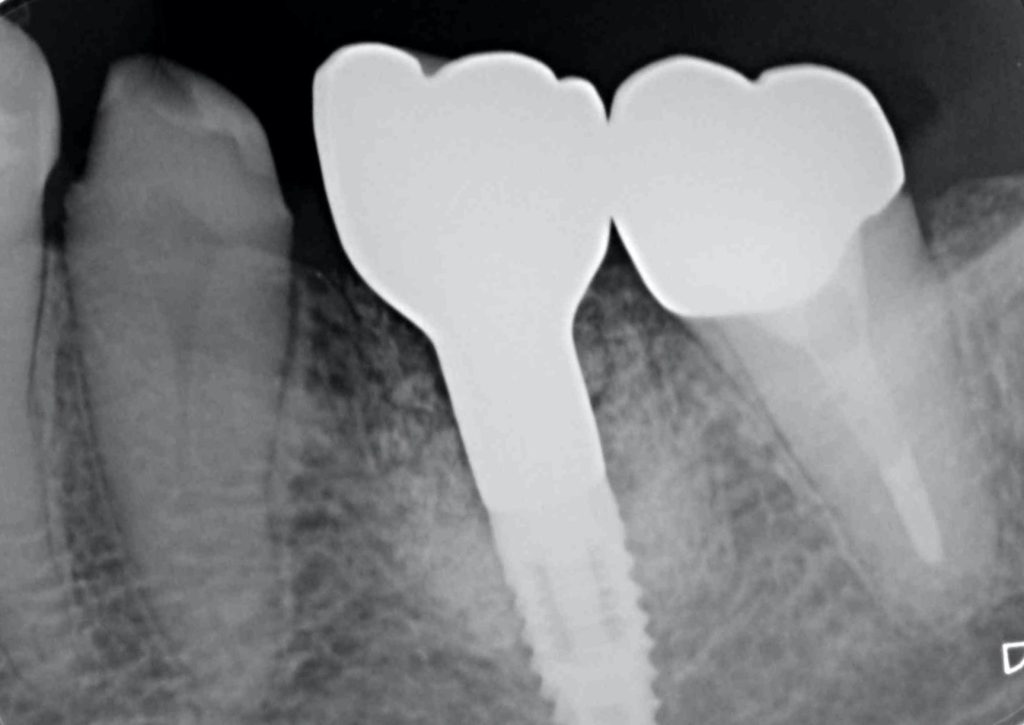

下記のケースは4年前から抜歯が必要ですとご指摘しておりました。

歯根破折を起こし、周囲の骨が炎症を起こしていました。